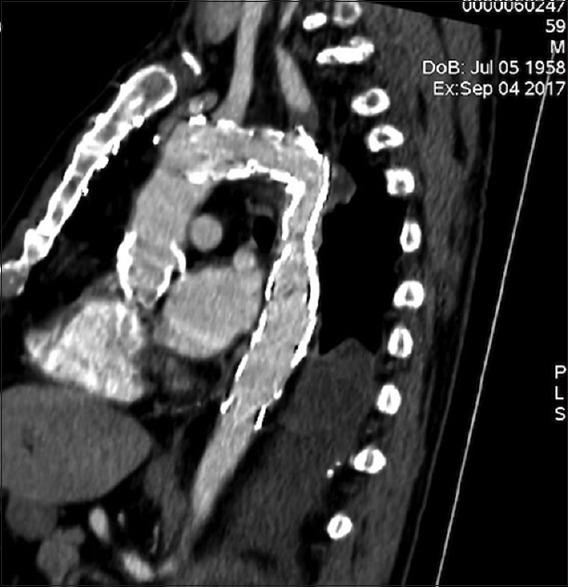

成人术后缩窄性假性动脉瘤血管腔内修复术中主动脉破裂:紧急植入挽救生命的覆膜支架。

Aortic rupture during endovascular repair of a postoperative coarctation pseudoaneurysm in an adult: Emergency lifesaving stent graft implantation.

We present a case with aortic rupture during an operation of thoracic endovascular aortic repair of an anastomotic pseudoaneurysm. This happened after the use of a low-pressure remodeling balloon inside the covered part of the deployed endografts. It was successfully treated with a second more centrally in the aortic arch-implanted endograft with full coverage of the left subclavian artery orifice. This patient had a history of surgically operated aortic coarctation.

摘要

我们报告一例在胸主动脉腔内修复吻合口假性动脉瘤手术过程中发生主动脉破裂的病例。这发生在已植入的覆膜支架移植物覆盖部分内使用低压重塑球囊之后。通过在主动脉弓更中心位置植入第二个完全覆盖左锁骨下动脉开口的支架移植物成功治疗了该病例。该患者有主动脉缩窄手术史。